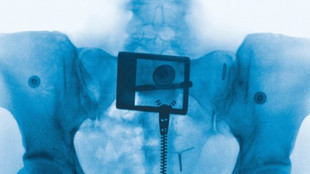

É stato presentato in anteprima stasera a Palmi il nuovo film dei Manetti bros., "US Palmese", nella sale dal 20 marzo, distribuito da "01 Distribution". Oltre ai registi, erano presenti i protagonisti del film, Rocco Papaleo, Blaise Afonso, Giulia Maenza e Max Mazzotta, oltre al produttore Pier Giorgio Bellocchio ed ai rappresentanti del distributore e della fondazione Calabria Film Commission. Nel cast anche Claudia Gerini, nel ruolo della poetessa Ferraro. "US Palmese" é una commedia sul calcio che si lega alla nuova narrazione della Calabria e delle sue migliori realtà. Una favola calcistica, intrisa di emozione e di allegria, in cui il battito del cuore s'intreccia con la voglia di credere ancora nei sogni. Il film, presentato in anteprima all'ultima edizione della Festa del Cinema di Roma ed all'International Film Festival di Rotterdam, è prodotto da Pier Giorgio Bellocchio, Manetti bros. e Carlo Macchitella. Una produzione "Mompracem" con Rai Cinema ed il sostegno della Calabria Film Commission, in associazione con Loka Film.